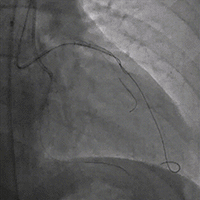

治疗方案(介入治疗·冠脉造影)

LCX近段30%狭窄,OM1 80%狭窄,OM2 90%狭窄,LAD近段100%狭窄,D1高位发出,80%狭窄。

冠脉造影

RCA中段支架内增生 80%,PL 100%。

双侧造影明确LAD开口位置和临近血管关系。